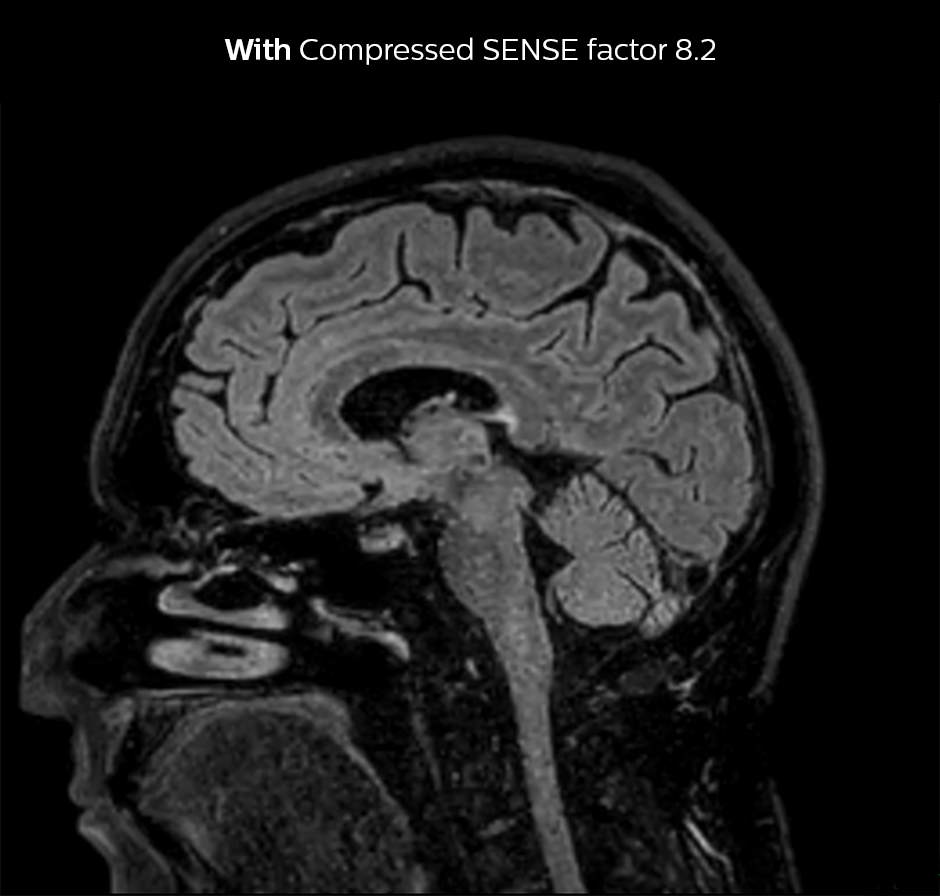

Dr. Sartoretti remembers how Compressed SENSE immediately impressed her in the first scans. “Our first sequence with Compressed SENSE was a 3D FLAIR in the brain on the Ingenia 1.5T, where we used a Compressed SENSE factor of 8.2. Then we tried a 3D TSE mDIXON post-contrast sequence with a CS factor of 7. In both cases the quality was really good.”

3D FLAIR, scan time 5:02 min, voxel size 1.1 x 1.1 x 1.1 mm, Ingenia 1.5T.

3D FLAIR, scan time 3:36 min, voxel size 1.1 x 1.1 x 1.1 mm, Ingenia 1.5T.